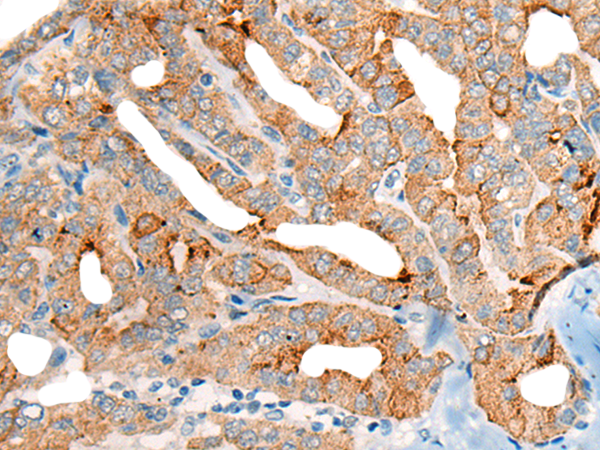

分类: 科研抗体货号: P02481别名: 4F2; CD98; MDU1; 4F2HC; 4T2HC; NACAE; CD98HC应用: WB,IHC反应种属: Human